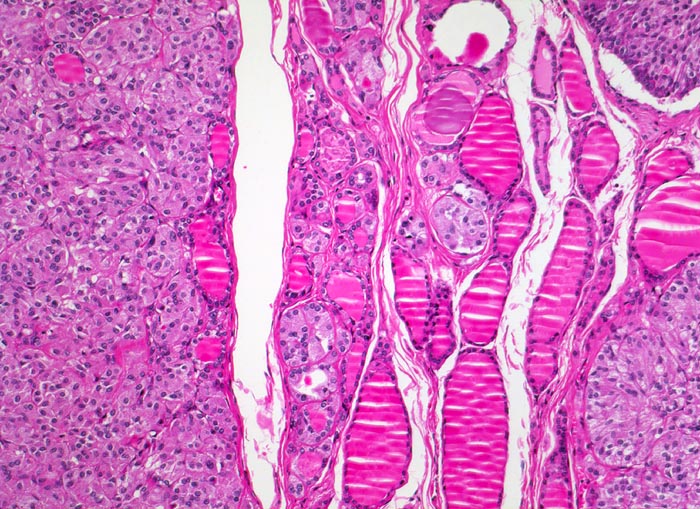

medulläres Schilddrüsenkarzinom bei MEN 2A

Überwiegend solide Tumorknoten aufgebaut aus relativ monomorphen Zellballen, zwischen denen schmale Bindegewebssepten verlaufen. Zwischen den Tumorknoten ist normales Schilddrüsenparenchym mit Herden von hyperplastischen C-Zellen erkennbar.

Mehrere scharf begrenzte weisse Knoten in beiden Schilddrüsenlappen von bis zu 8mm Durchmesser.

Beim Vater der Patientin wurde ein bilaterales Phäochromozytom diagnostiziert und in der Folge eine multiple endokrine Neoplasie vom Typ 2A. Im Familienscreening wurde bei der Patientin eine Mutation im Ret-Protoonkogen nachgewiesen und eine prophylaktische Thyreoidektomie durchgeführt.

Histologie

100